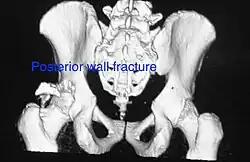

| Posterior wall | This is the most common variety of acetabular fracture. It typically occurs due to dashboard injury; when a person travelling in a vehicle involved in a head-on collision, the force applied over the flexed knee travels along the femur bone to the head of the femur, breaking the posterior wall of the acetabulum. The head of the femur is dislocated outside the joint. | T shape | When a transverse fracture also had a vertical fracture line, it is called a T shape fracture. Here the innominate bone is broken in such a way that all three parts of it, the ilium, the ischium and the pubis are separated from one another. This is a three part fracture. Though both columns are broken, the weight bearing dome is still attached to the main part of the ilium and hence it is not a true fracture of both columns.

- Posterior wall fracture: Iliac oblique and obturator oblique views

Posterior wall fracture as seen on 3-D CT scan

Posterior wall fracture as seen on 3-D CT scan -